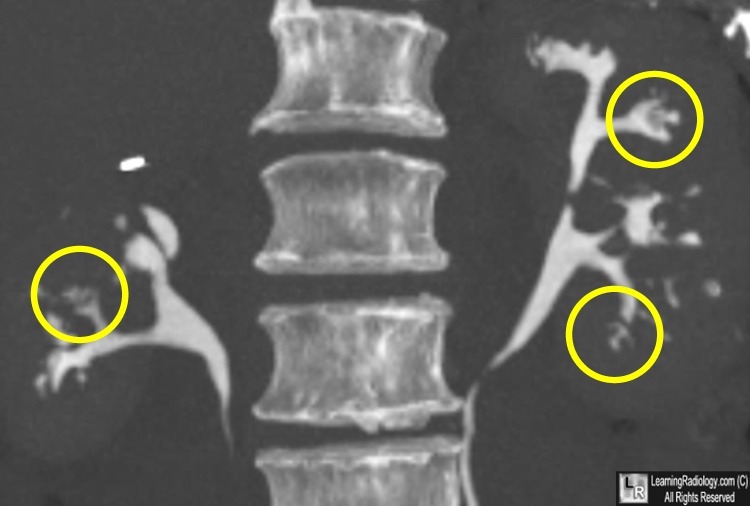

Diagnosis?

Medullary nephrocalcinosis.

95% of cases are due to primary hyperparathyroidism, distal renal tubular acidosis (type 1), or medullary sponge kidneys.

But it can be caused by anything that causes hypercalcemia, hypercalciuria, or hyperoxaluria (others include milk alkalai syndrome, multiple myeloma, hypervitaminosis D, Cushing syndrome).